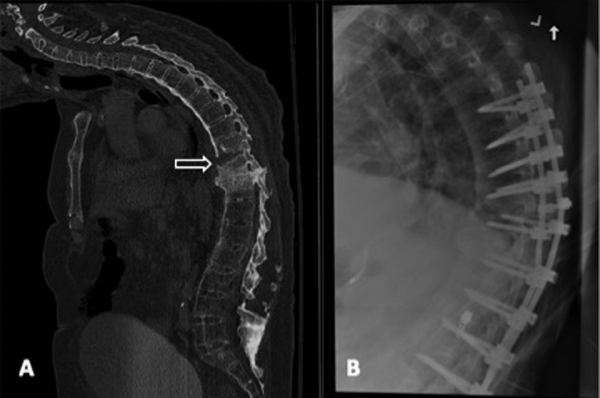

A 71-year-old male with ankylosing spondylitis who sustained a ground-level fall resulting in T9 to T10 hyperextension fracture and complete spinal cord injury. A, Sagittal computed tomography demonstrating the T9 to T10 hyperextension fracture (arrow). B, Lateral thoracic radiograph demonstrating the operative management consisting of T6 to L2 posterior spinal fusion.